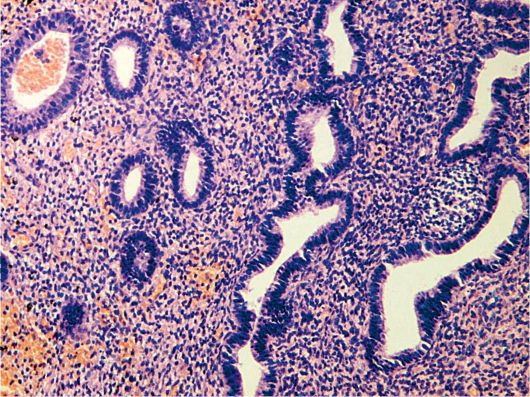

Практически любая форма диагностируется ультразвуковым исследованием. Часто назначается зондирование и эхография. Если подозревается гнойная форма необходимо проверить матку специальным оптическим прибором – кольпоскопом. Помимо кольпоскопии, при эндометрите назначается гистероскопическое исследование, с помощью которого можно осмотреть стенки матки и получить выскабливаемый материал для того, чтобы диагностировать хроническое течение.